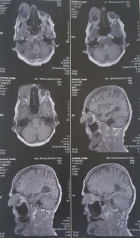

An 86-year-old woman was referred to our clinic with a history of progressive, painless swelling over the right upper eyelid, for the past 5 months (Figure 1). In this region of masses was present an ulcerated swelling (Figures 1 & 3). Initially the tumor was too small but it was rises very rapidly (Figure 2). There were no systemic symptoms including loss of appetite, loss of weight, fever or a headache. No significant medical, surgical or family history could be elicited (Figures 2 & 3). An MRI of ocular area revealed a 45x40x35 mm solid mass in the upper eyelid with infiltration of rectus muscle but there was no extraconal, intraconal, intraocular, intracranial or paranasal sinus involvement. No bony erosions were noted (Figure 4) MRI.

Figure 4: An MRI scan of the ocular space revealed a 45*40*35 mm, malignant tumor on the right upper eye lid and lacrimal gland.